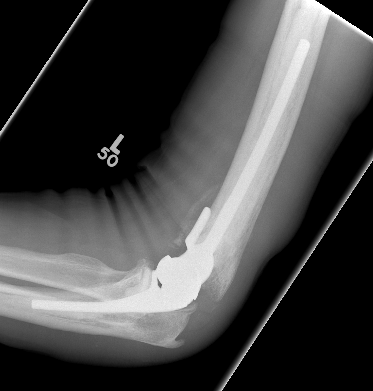

OTA / AO Classification

Type A: Extra-articular fracture

Type B: Partial articular fractures

Lateral condyle Medial condyle

Type C: Complete articular fractures

CT scan